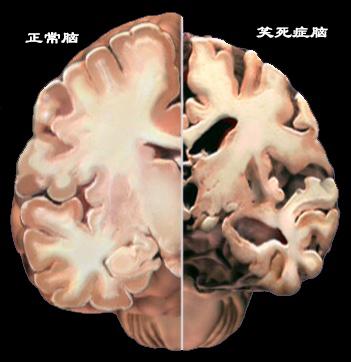

于是,他将正常人的脑和笑死症的脑进行对比,可以明显的看到笑死症患者的脑存在这明显的体积萎缩、变性和坏死。